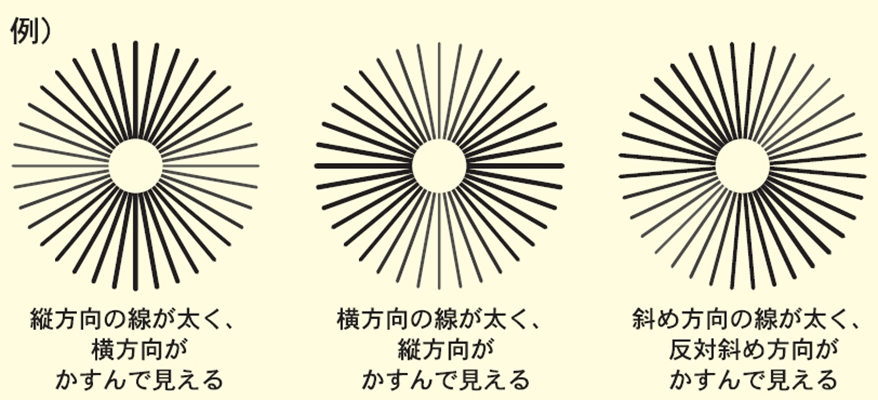

A:判斷自己有沒有散光,最簡單的方法是使用散光表來測試。散光表是一種簡單、方便的方法,但是它的準確度不是特別精確。在配鏡的情況下一般再用裂隙法,或者是交叉圓柱鏡法來精調散光的度數。散光表在網上可以看到,它類似於鐘錶的盤面,有12個數字。各個鏡線……